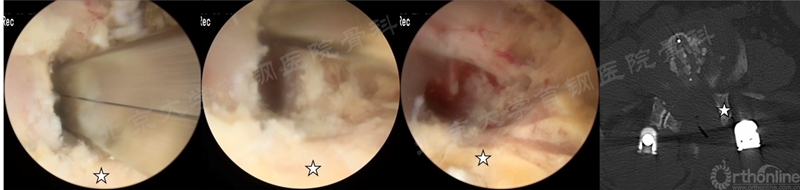

P-TLIF在UBE/BESS文献中未被直接提出,但通过文献中对手术步骤的描述笔者发现在2020年以后的BE-TLIF的文献中,多数作者不再将关节突关节完全切除,而是切除上关节突的内侧部分来完成减压和融合,这包括Dong Hwa Heo、Seok Bong Jung和中国学者Qingcheng Gao等。

我中心进行BE-TLIF时也是根据减压和植入Cage的需要来切除同侧关节突关节,部分患者术后关节突关节部分保留,这种手术方式准确来说可称为BE-PTLIF(如图11)。

图11 我中心进行的一例UBE-PTLIF术中照片及术后CT资料(☆为保留的上关节突,图片来源于我中心,转发需注明出处)